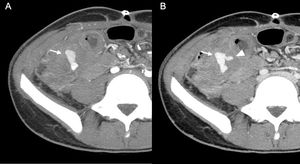

14-year-old male with abdominal pain, hypotension and rectorrhagia after recent surgery for acute appendicitis with peritonitis. Axial maximum intensity projection reconstructions of CT angiography of the abdomen and pelvis in arterial (A) and venous (B) phases showing a bilobed pseudoaneurysm (arrow) of the ileocolic artery in the surgical bed. It is accompanied by a focal area of active contrast extravasation (arrowhead) that is evident in the venous phase (B), related to bleeding due to rupture of the pseudoaneurysm.